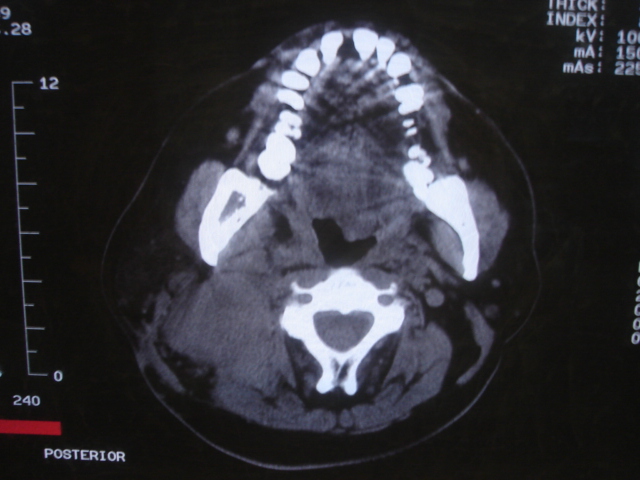

患者 男 61  甲状腺ca术后7年 颈部淋巴结转移

声门下区表面不光整,增厚呈局限性突起,未见局部浸润.

考虑----颈部淋巴结转移,不排除---喉乳头状瘤可能.

颈部多个淋巴结增大,结合甲状腺ca术后7年病史考虑转移。

另声门区不规则突起,建议喉镜检查!

右侧颈部淋巴结转移,右声带乳头突起,乳头状瘤可能性大。